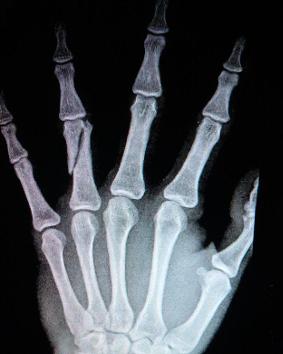

♥指骨骨折

指骨骨折的发病率很高,是手部常见的骨折,亦称竹节骨骨折。多为直接外力引起,多发性居多,骨折后移位明显,三节指骨移位方向不一。一般可徒手复位,将远端对近端尽量达到解剖复位,不能有成角或旋转移位。能在功能位固定为理想,对于不稳定性指骨骨折和功能位不能保持良好复位者,可考虑手术复位克氏针内固定。